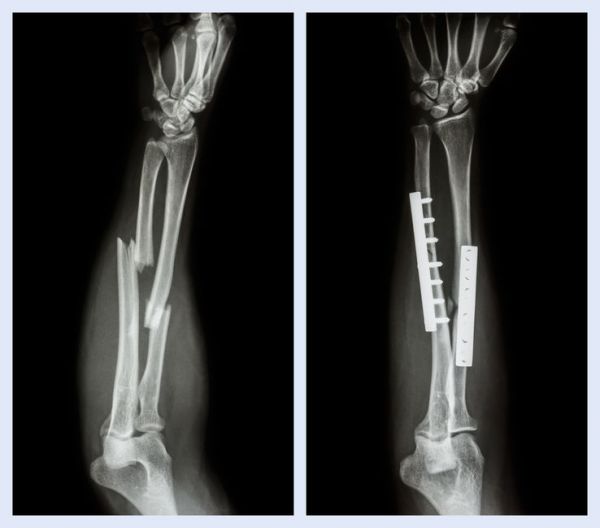

Como é feito o diagnóstico?Além da história clínica e do exame físico, a utilização de alguns exames de imagens auxilia no diagnóstico e no planejamento da conduta terapêutica. A radiografia (RX) é o exame mais acessível e o mais utilizado para essa finalidade.

Como é feito o Tratamento Cirúrgico? As indicações mais aceitas para o tratamento cirúrgico de fraturas agudas do antebraço são fraturas expostas, comprometimento neurovascular associado e politraumatismo. Outras indicações são os grandes desvios, cotovelo flutuante (fratura do antebraço e do úmero no mesmo lado), idade acima de 10 -12 anos na presença de grande deformidade e falha do tratamento conservador. As demais situações devem ser avaliadas caso a caso. Dentre as principais técnicas empregadas, está a utilização de placas e parafusos. Em crianças, também podem ser utilizados fios (pinos) e hastes.